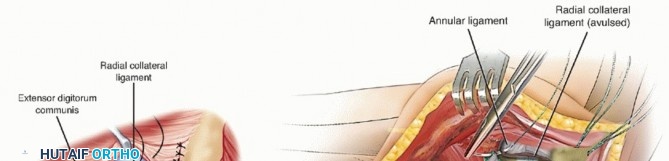

The common extensor tendon is split longitudinally at the middle aspect of the radial head, and the underlying radial collateral and annular ligaments are incised (TECH FIG 2A).

The humeral origin of the radial collateral ligament and the overlying extensor muscles are elevated anteriorly off the lateral epicondyle to improve the exposure if needed (TECH FIG 2B).

- TECH FIG 2 • A. The common extensor tendon is split longitudinally at the middle aspect of the radial head, and the underlying radial collateral and annular ligaments are incised. The forearm is pronated to protect the posterior interosseous nerve. (continued)

TECH FIG 2 • (continued) B. The humeral origin of the radial collateral ligament and the overlying extensor muscles are elevated anteriorly off the lateral epicondyle to improve the exposure if needed.